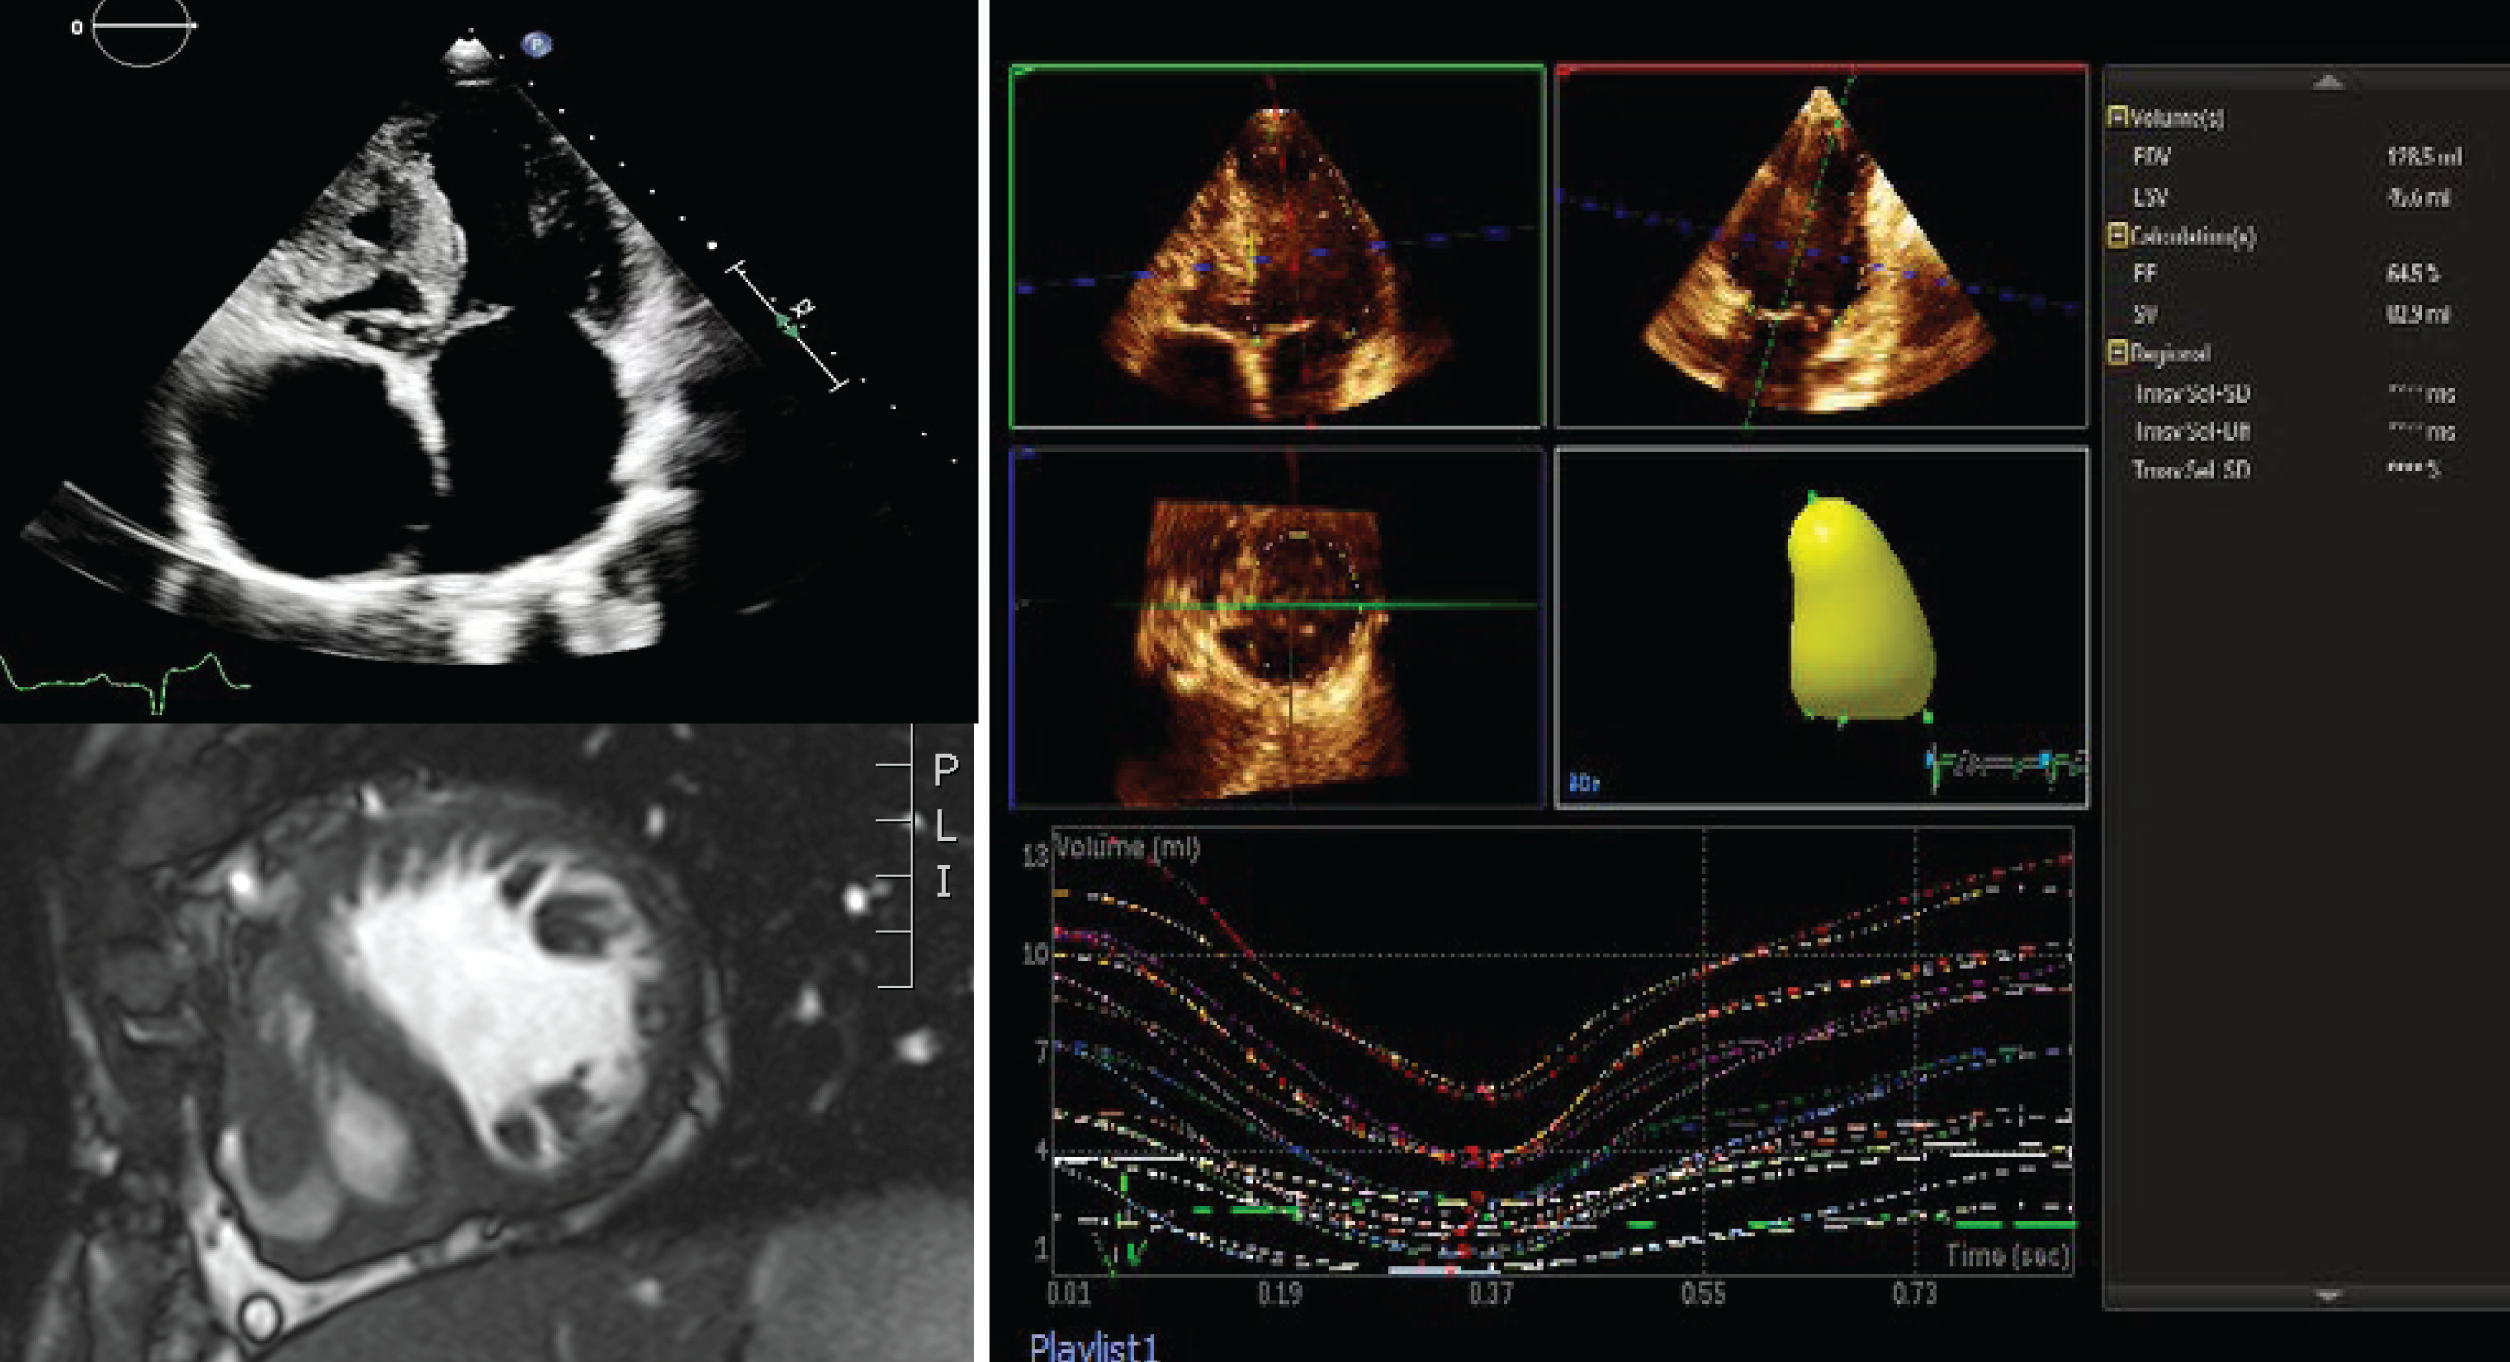

For 3D acquisitions, an x-plane of the ventricle was performed to ensure inclusion of the planes within the volume to be acquired. Spatial and temporal resolutions were optimised by narrowing sector width, optimising depth and focus. A 3D full volume setting was applied and images were taken over 4 heart beats in all cases during end-expiratory breath-holding. Volume analysis was performed off-line using the Q-Lab (Philips, Netherlands) 3D left ventricular volume software package for both systemic left and right ventricles; using the same definition for end-diastole and end-systole as for 2D acquisitions (Fig. 1). The mean frame rate used was 27 Hz with a range from 21 to 59 Hz and time taken to acquire the 3D images and perform the post-processing analysis of volumes took between 3 and 5 minutes.

2.2 Cardiac Magnetic Resonance Imaging

CMR was performed according to standard protocols with a 1.5 T scanner (Siemens, Avanto) during end-expiratory breath-holding with retrospective ECG gating using steady state free precession (SSFP) cine imaging (Fig. 1). In brief, following acquisition of scout images in the vertical, horizontal and 3-chamber axes, SSFP images were acquired with 7 mm thickness; 3 mm gap from the atrioventricular valve plane through the apex. Sequence parameters were as follows: echo time 1, 2 ms; repetition time 60 msec, flip angle 79 degrees; 25 phases per cardiac cycle; number of excitation 1; FOV 300 mm, in plane spatial resolution 1.6 mm × 1.2 mm. Analysis of all CMR images was performed by a single observer (level 3, European Association of Cardiovascular Imaging) with 3 years’ experience in CMR in imaging adults with congenital heart disease, using semi-automated quantification (Circle CVi42, Calgary, Canada). The observer was blinded to the results derived from echocardiography. Quantitative parameters (ventricular EDV, ESV, mass, stroke volume) were derived by semi-automated blood-pool thresholding using non-rounded endocardial contours, and including papillary muscles and ventricular trabeculations in the blood pool both in systole and diastole. The standard CMR technique requires that both the systemic and the atretic ventricle are included in volume analysis [14].

Figure 1: Fontan ventricle in a patient with tricuspid atresia. TTE of the Apical 4 chamber view (top left), CMR short-axis (bottom left) and 3D echocardiography volume of the systematic ventricle (right). (Abbreviations: 2D = two dimensional; 3D = three dimensional; CMR = cardiac magnetic resonance; TTE = transthoracic echocardiography)